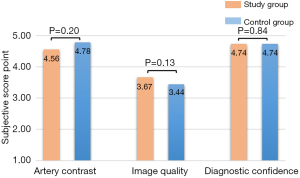

For the subjective evaluation, all images in both groups could display all coronary arteries clearly and had strong confidence for diagnosis (Figure 2). The image contrast score (4.56±0.57 vs. 4.78±0.42), overall image quality score (3.67±0.47 vs. 3.44±0.51), and diagnostic confidence (4.74±0.44 vs. 4.74±0.45) had no statistically significant differences (P>0.05) (Figure 3).